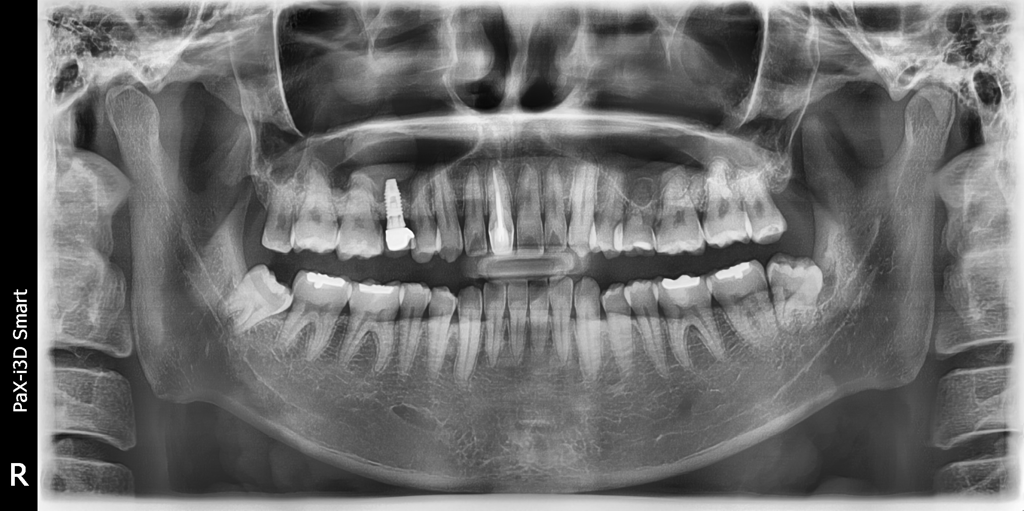

유치로 인해 임플란트 한 후 10여년이 지났는데요

임플란트 한 부위쪽 잇몸만 유난히 튀어나와있는데요

유치로 인해 임플란트 한 경우 이런 증상이 흔한가요?

뼈 모양에 따라 임플란트가 튀어나와 보일 수 있으며 임플란트 했어도 교정치료는 가능합니다.

유치로 인한 임플란트는 영구치가 선천적으로 결손 상태라 유치를 최대한 오래 쓰다가 임플란트를 하는경우가 꽤 있습니다.